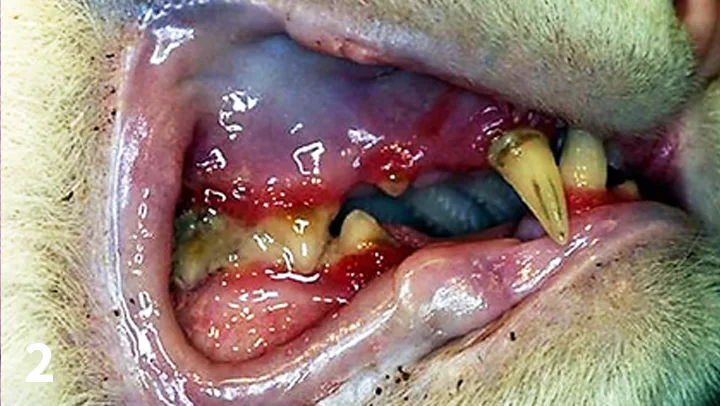

Stomatitis is defined as an inflammation of the mucous membranes anywhere in the oral cavity.1 This inflammation is more severe than gingivitis or periodontitis because it can extend into the submucosal tissues.

Gingivostomatitis–chronic active inflammation of the mucosa and submucosa–presents with erythematous, ulcerative and/or proliferative lesions commonly found on the gingiva, buccal mucosa, lips, palatal glossal folds, lateral pharyngeal walls, and lateral aspects of the tongue.2-4 (See Figure 1.) No sex, age, or breed predilection exists. The median age of patients with this disease is 7 years.2

Intraoral image of intubated cat showing marked swelling and redness of caudal oral mucosa.

FIGURE 1

Gingivostomatitis showing the extent of oral inflammation. All photos courtesy of the author unless noted otherwise.

The cause is currently unknown, but bacterial, viral, and immunological causes (eg, plaque bacteria, calicivirus, FHV-1, coronavirus, Bartonella henselae, FeLV, FIV, immune reaction) are being investigated.2-4 The most common signs in cats with this disease include halitosis, blood-tinged saliva, ptyalism, dysphagia, difficulty opening the mouth, and weight loss. These cats also become less active, show reluctance to groom themselves, and may become aggressive.2 Caution must be taken when examining these patients’ mouths because they are in pain.

Treatment is a combination of medical and surgical therapy2-4 aimed at controlling the disease. Relapses may occur. Medical therapy may include antibiotics, corticosteroids, pain medications, immunostimulants, and immunosuppressants.2,3 Extracting the teeth in the inflamed areas has shown the best outcome.5 In general, 60% of cases that have surgical intervention will have complete resolution, 20% will have minimal inflammation, 13% will have partial improvement but require continued medical therapy, and 7% will show no improvement.2